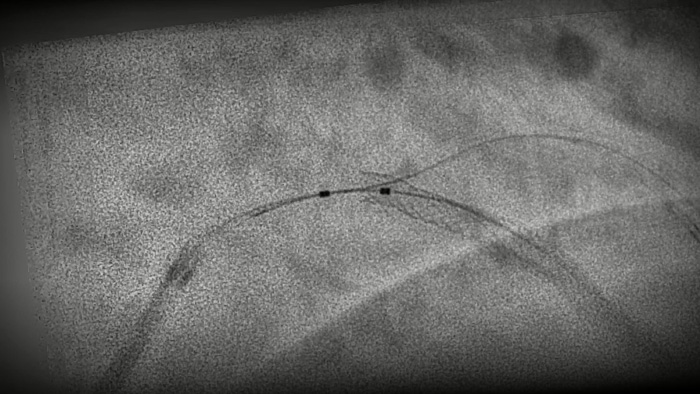

StentBoost Live10 le ayuda rápidamente a verificar el posicionamiento antes y después de desplegar balones, stents y dispositivos intracoronarios para ver la implementación y confirmar la expansión completa. Y todo ello se realiza en tiempo real, por lo que ya no tendrá que esperar a recibir nuevas imágenes antes de reposicionar.